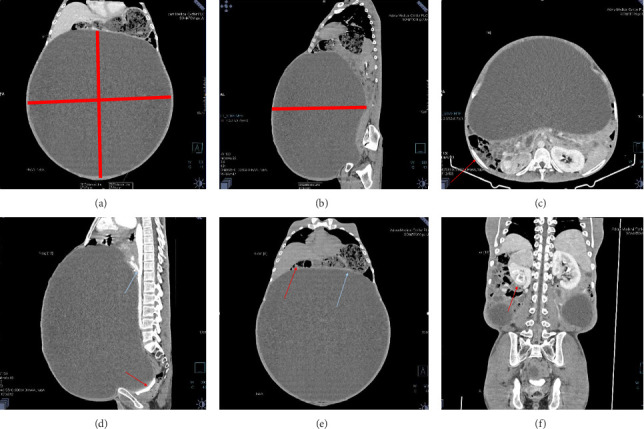

Mesenteric cysts are rare benign intra-abdominal tumors that are usually asymptomatic and diagnosed incidentally while being investigated for other conditions or their complications. Surgical excision remains the primary treatment option. Here we present the case of a 30-year-old male with progressive abdominal distension, initially misdiagnosed with liver disease and refractory ascites, leading to inappropriate diuretic therapy. Subsequent imaging revealed a giant mesenteric cyst, which was successfully managed with complete surgical excision.